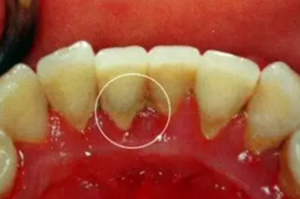

牙周炎主要是由局部因素引起的牙周支持組織的慢性炎癥。如果牙齦炎沒有及時治療,炎癥可由牙齦向深層擴散到牙周膜、牙槽骨和牙骨質而發展為牙周炎。

1.png

牙周炎早期多沒用明顯癥狀,因此易被忽視。等到發現時,已經比較嚴重,甚至必須拔牙。因此,為了預防牙周炎,春天牙科牙醫再次給大家普及下牙周炎的相關知識。

2.png

(1)齦上牙結石

位于齦緣以上的牙面上,肉眼可直接看到。在牙頸部沉積較多,特別是在大涎腺導管開口相對處,如上頜磨牙的頰側和下頜前牙的舌側沉積更多。齦上牙石中無機鹽的主要來源是唾液中的鈣、磷等礦物鹽。